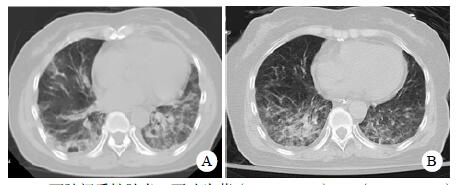

| A:右侧丘脑、左侧岛叶病变,伴脑室扩张;B:双侧脑室钻孔引流术后改变,脑室扩张较前(2019-09-29)好转,右侧丘脑、左侧岛叶病变伴出血 图 2 患者2019-09-29头颅CT平扫(A)和2019-09-30头颅CT平扫(B) |

转入ICU后呼吸机辅助通气、甘露醇100 mL/8 h静滴脱水、头孢呋辛1.5 g/12 h静滴抗感染,肠内营养等支持治疗。当晚血常规:白细胞13.3×109/L,中性粒细胞百分比85.3%,C反应蛋白17.1 mg/L,降钙素原0.64 ng/mL。脑室外引流术后次日血化验:白细胞16.6×109/L,中性粒细胞百分比92.8%,C反应蛋白78.4 mg/L;从脑室外引流管留取脑脊液检验:有核细胞6×106/L,红细胞1 960×106/L,蛋白含量1.717 g/L,葡萄糖4.72 mmol/L,细菌培养阴性,涂片未找到细菌;复查头颅CT示:脑室扩张好转,右侧丘脑、左侧岛叶病变伴出血(图 2);胸部CT示,两肺间质性肺炎下叶为著,较前(2019年6月21日)部分好转(图 3)。考虑到炎症指标升高,遂改哌拉西林他唑巴坦3.375 g/12 h静滴抗感染。此后经脑室外引流管反复留取脑脊液送检涂片及培养均阴性。术后第5天行“导航下立体定向颅内病灶活检术+双侧omaya囊置入术”,术中穿刺液呈黄色黏稠脓性,考虑脑脓肿,留取脓液送高通量测序(next-generation sequencing, NGS),并升级为美罗培南2 g/8 h联合利奈唑胺0.6 g/12 h静滴抗感染治疗。术后第7天患者突发血压升高、瞳孔不等大,昏迷程度加深;急查头颅CT示,双侧脑室钻孔引流术后改变,双侧侧脑室引流管走形区出血伴血肿形成;右侧丘脑区积液、积血,双侧脑室积血新发(图 4),甘露醇加量至250 mL/8 h联合地塞米松5 mg/6 h静滴加强脱水;当日术中脓液高通量测序结果回报:皮疽诺卡菌(序列数52 867个)、支气管戈登菌(序列数10个)。确诊脑诺卡菌病,抗菌治疗方案改为亚胺培南西司他丁0.5 g/6 h静滴,联合利奈唑胺0.6 g/12 h和复方磺胺甲恶唑片(0.48 g/片)3片/6 h口服。此后患者仍伴低热,炎症指标呈上升趋势。术后2周患者再次突发血压升高、瞳孔不等大、对光反射消失、神志深昏迷,急查头颅CT示再发脑疝(图 5),急诊行“去骨瓣减压术+脑内血肿清除术”,术后患者仍呈深昏迷状态,双侧瞳孔散大、对光反射消失,次日自动出院。